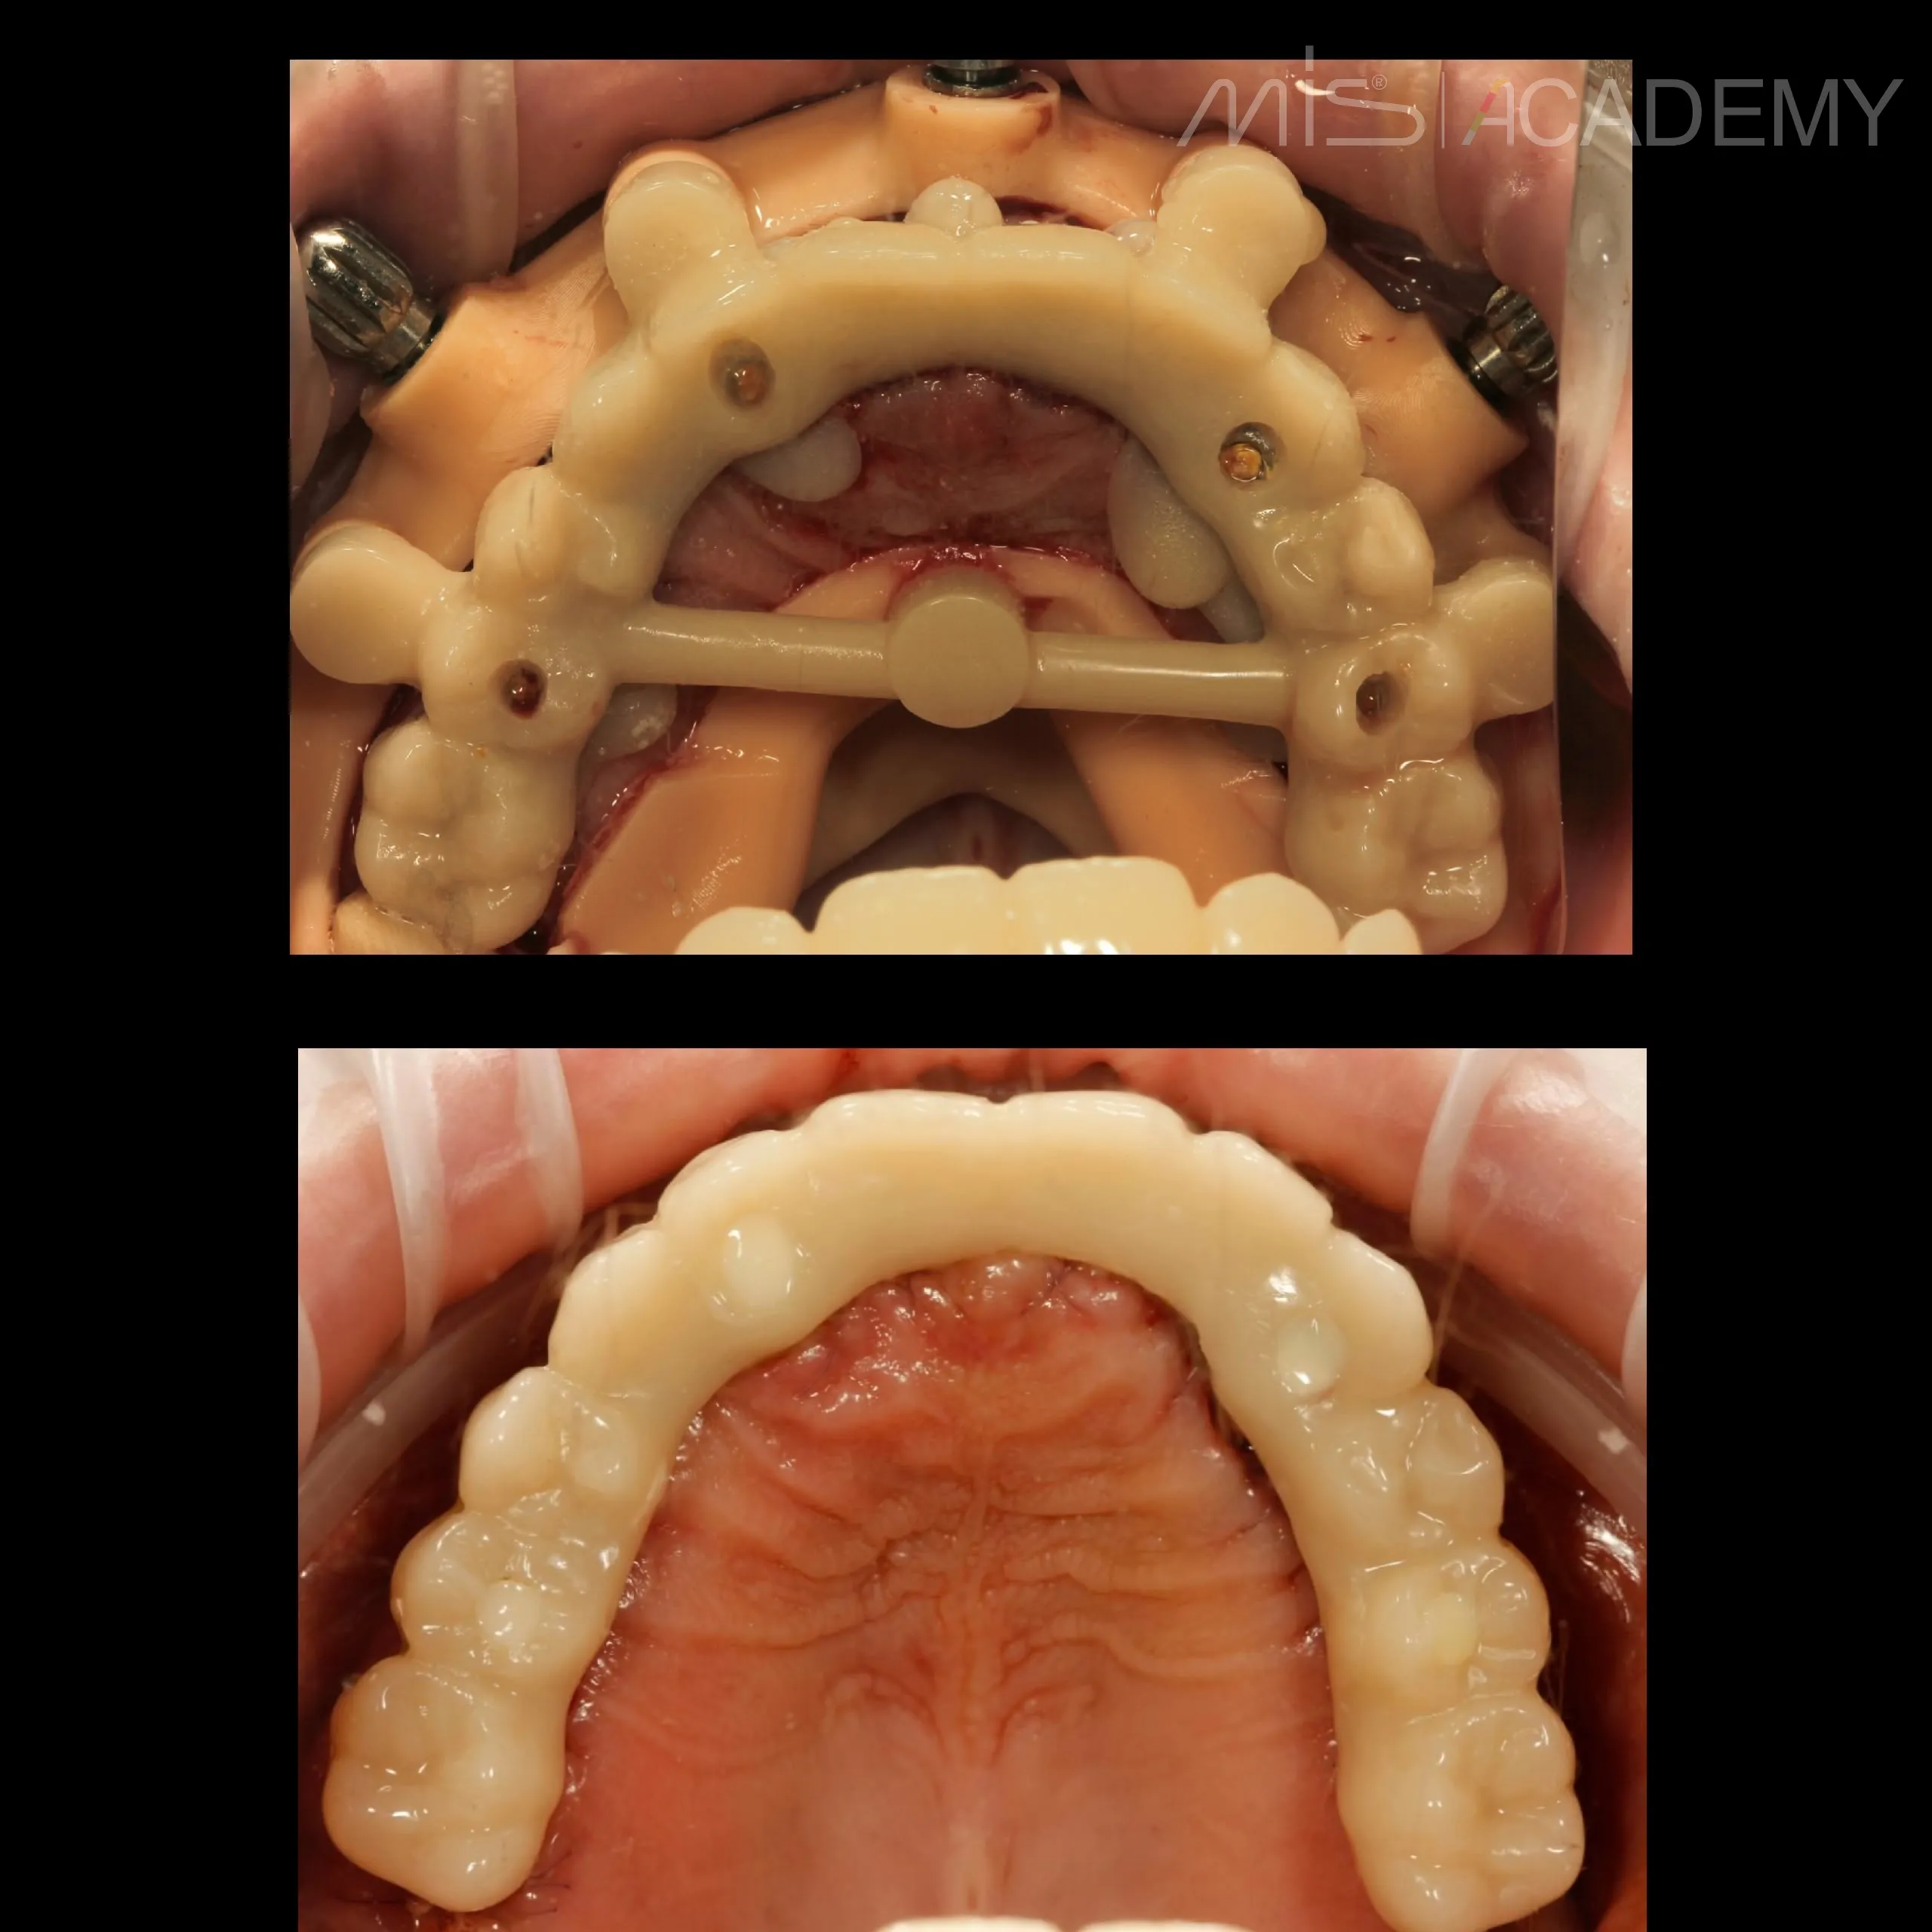

— Серия шаблонов.

— 4 имплантата MIS C1 + 4 connect-абатмента.

— Балка-интросварка.

— PMMA.